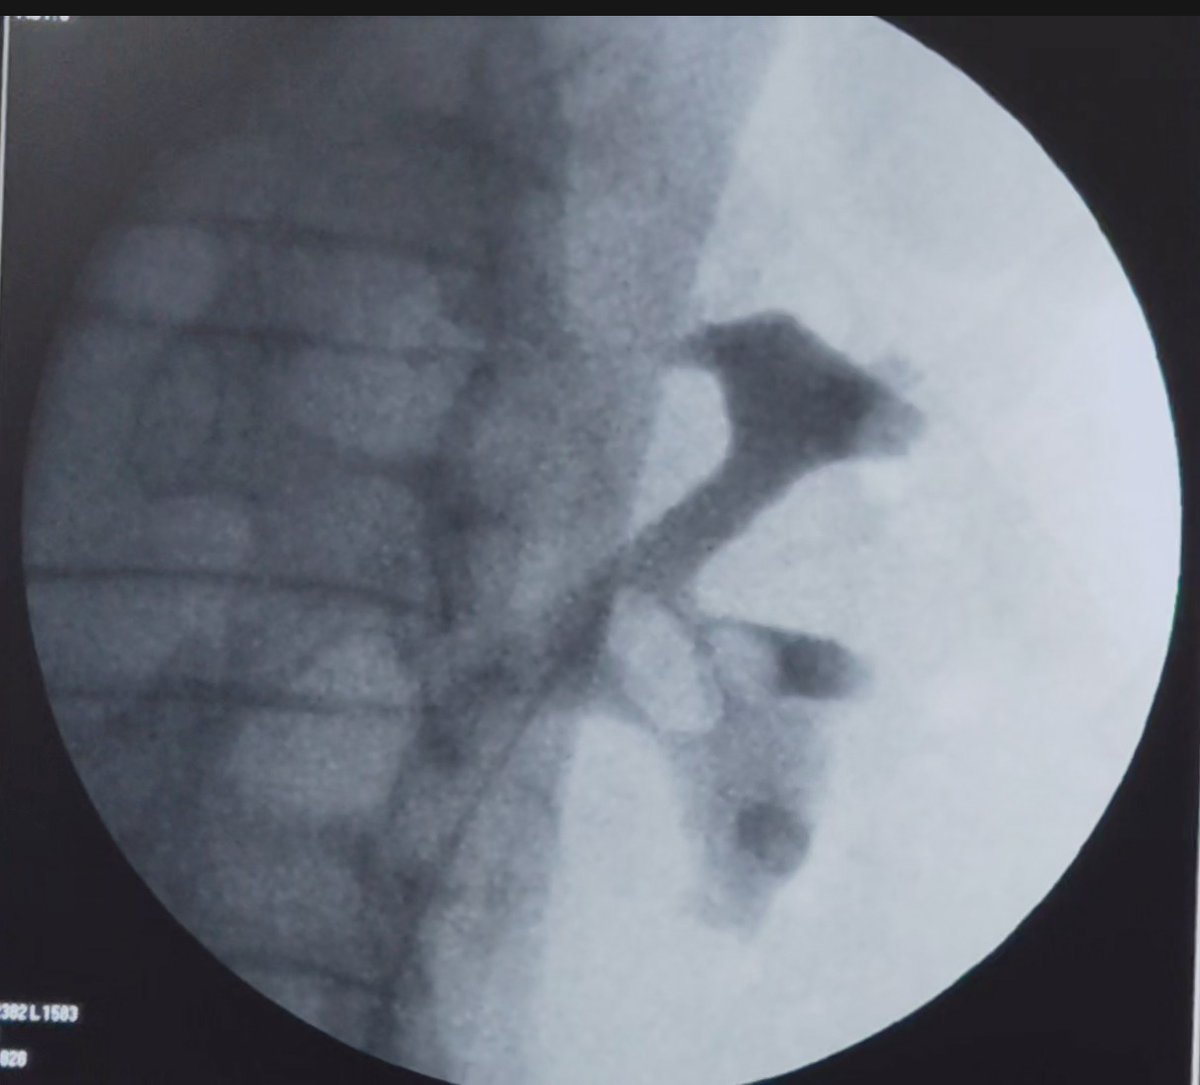

🔹 PCNL